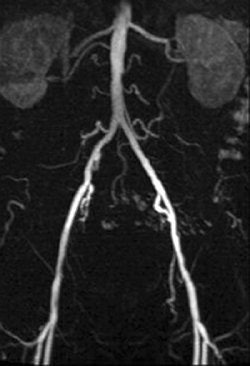

| A 78-year-old man with peripheral arterial occlusive disease. Lumbar arteries are evident with both MRI acquisition techniques. Iliac axis has good runoff on both sides after percutaneous transluminal angioplasty (above). Anteroposterior maximum intensity projection 3D fast low-angle shot (FLASH) intra-arterial MR aortogram obtained with standard technique (below). |